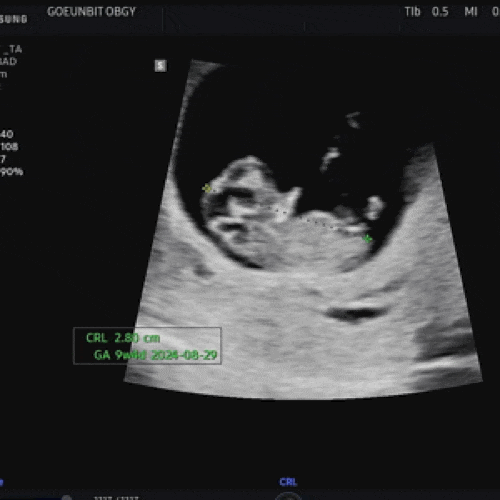

원래도 몸을 엄청 생각하는 편인데, 임신하니 더 그렇다.. 입덧이 사라지니 애기를 위해 고기를 꼭 챙겨먹...